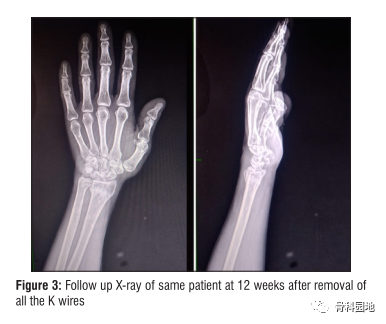

6周结束时,去除剩余的克氏针和夹板,并开始物理治疗[图3]。